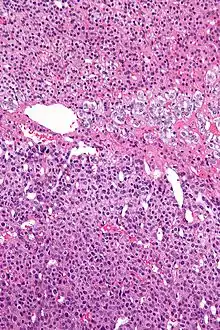

Макроскопічно адренокортікальна карцинома часто є великою солідною пухлиною жовтуватого кольору, на розрізі визначаються ділянки крововиливів і некрозу. При мікроскопічному дослідженні пухлини визначаються атипові клітини з мітозами.